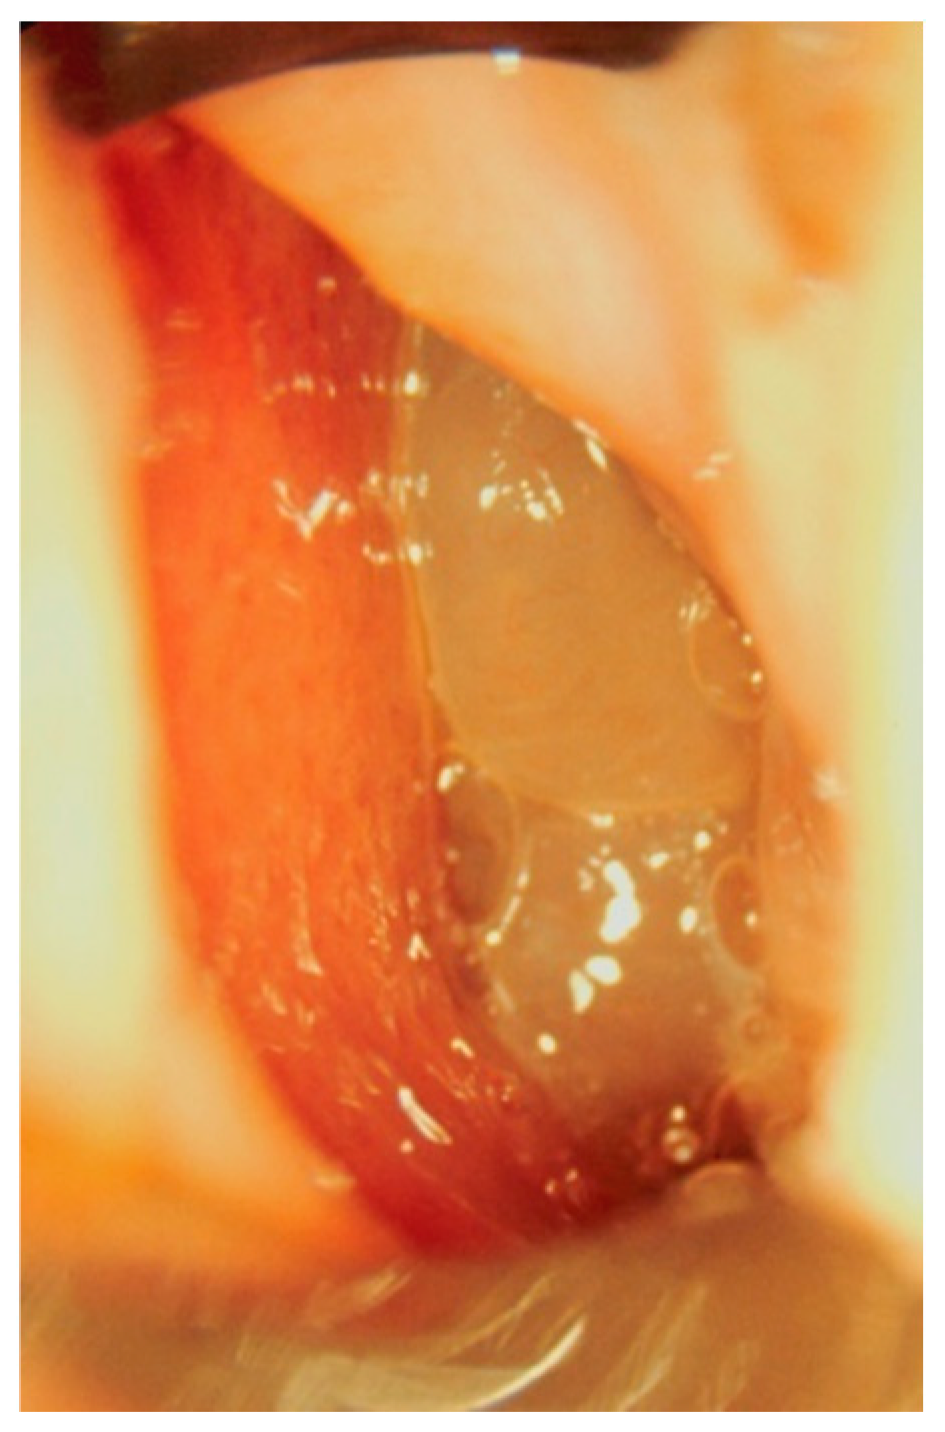

Clinical Manifestations and Diagnostic Methods